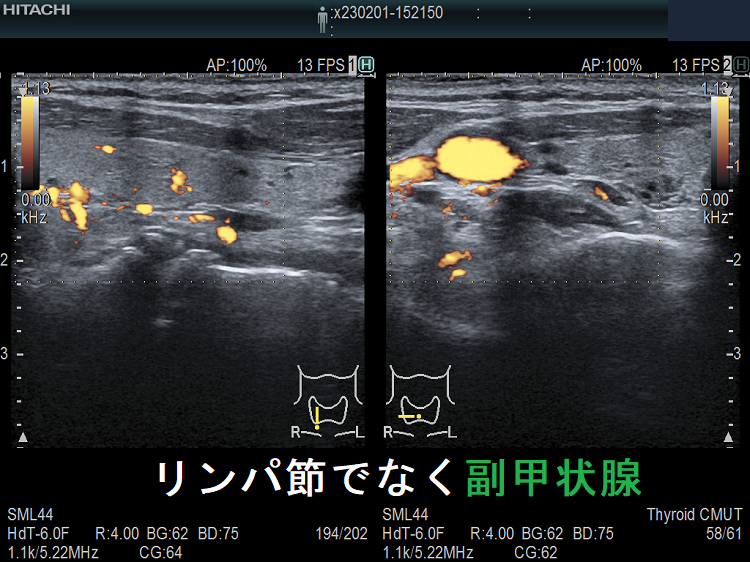

副甲状腺腺腫のように見えるも、実はただのリンパ節

副甲状腺腺腫との違いとして、リンパ節では

- 内部血流が無く

- リンパ門が存在します(ここだけ血流があります)

ケース③